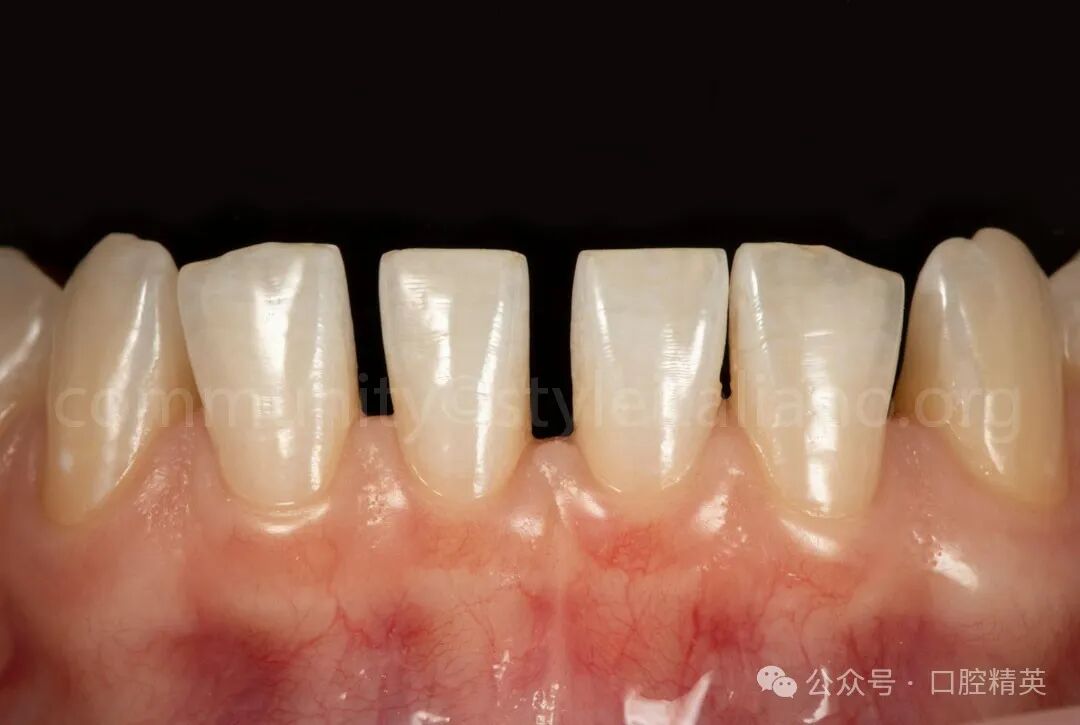

图10 修复后1周,修复体的最终外观显示出最佳的美学效果

修复后的牙齿呈现出自然、和谐的外观。这种方法保留了天然牙齿结构的完整性,促进了长期的口腔健康,并最大限度地减少了并发症的风险。利用CAD / CAM技术可以制作出高精度、个性化的修复体,而免预备技术可以减少患者的不适感和治疗时间。

这个案例突出了现代数字牙科如何在最小的干预下提供出色的功能和美学结果。